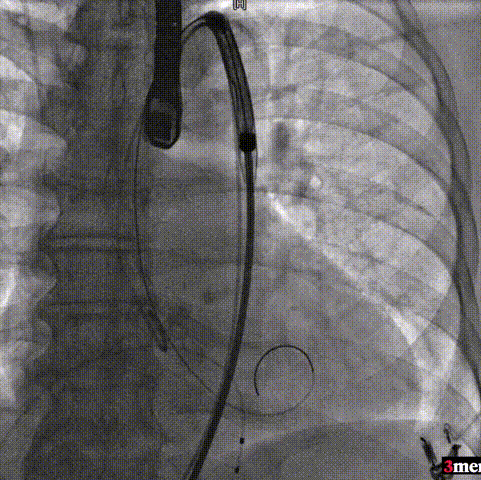

手术过程回顾:

主动脉根部造影

直头导丝跨瓣

球囊预扩

输送器过弓

瓣膜定位

瓣膜释放至工作位

瓣膜脱钩

球囊后扩

术后超声提示患者跨瓣压差即刻显著下降,反流量轻微。术中未出现相关并发症,术后患者心功能持续得到改善,效果良好,圆满取得此次手术成功。